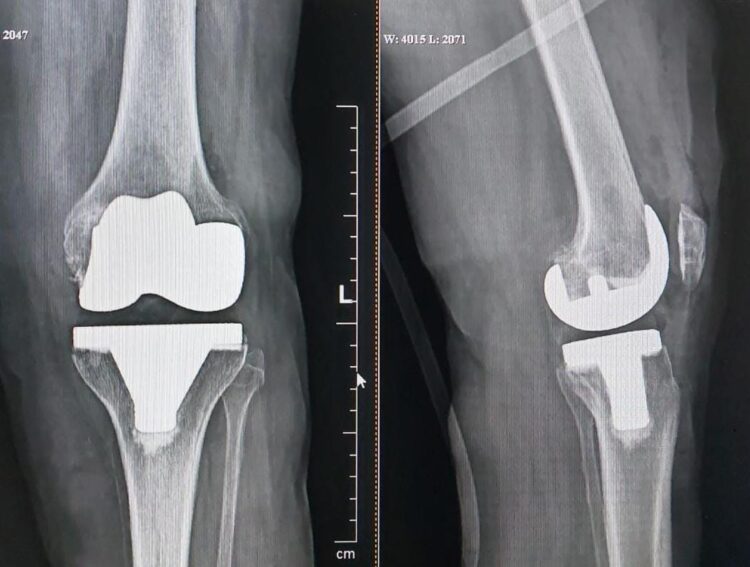

• تعویض مفصل زانو: در موارد بسیار شدیدی که آرتروز پیشرفته ایجاد شده است، ممکن است نیاز به تعویض کامل مفصل زانو باشد.

تعویض مفصل زانو به دلیل پای پرانتزی